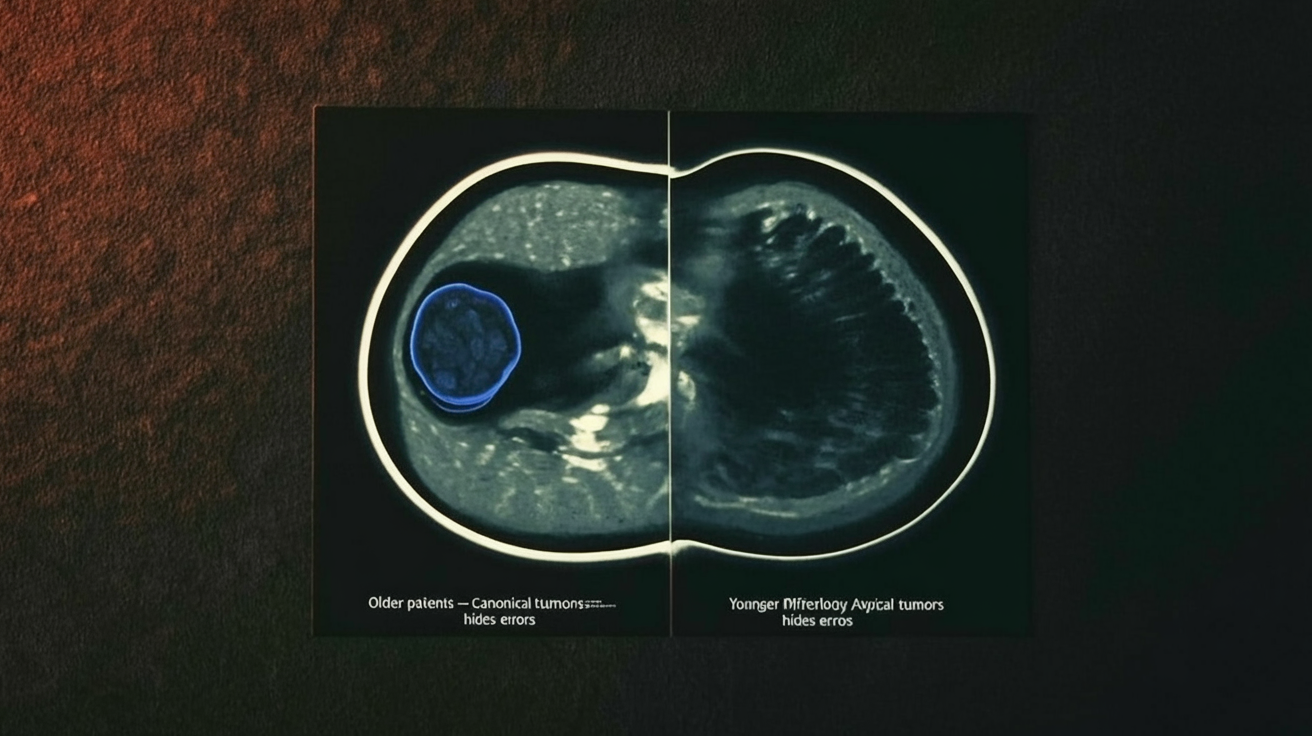

Younger patients break segmentation models, it’s qualitative, not just noisy

The comforting story would be: “Younger breasts are denser, so the labels are a bit messier. Clean up the noise and fairness improves.”

The MAMA‑MIA audit tears that up.

The tumors themselves differ.

They’re larger, more variable in shape, and embedded in backgrounds that look less like the “canonical” cases the model has seen. It’s not “more of the same” difficulty; it’s different kinds of anatomy and pathology, a qualitatively different distribution.

That distinction matters. If age bias were mostly about noisy labels, you could treat it as a cleaning problem. But if the morphology is different, fairness is a representation problem: the model simply doesn’t have the right vocabulary of shapes and appearances to do the job.

Automated labels are built from that same defective vocabulary.